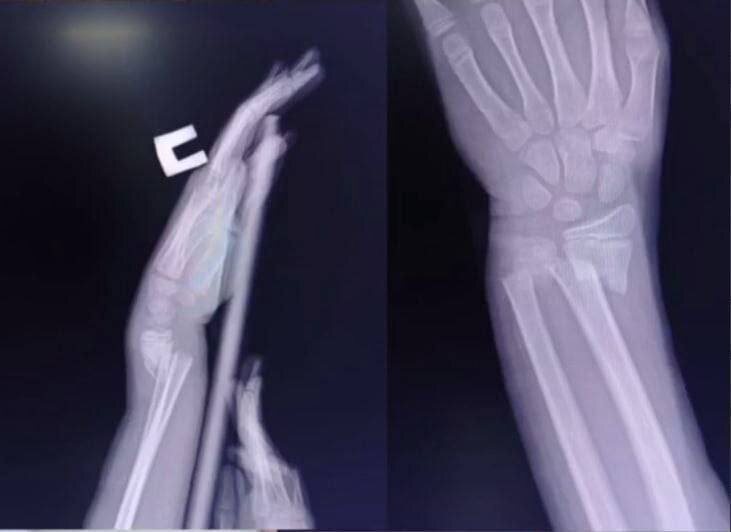

😱В Россию пришел опасный тренд из TikTok — Skull Breaker Challenge («разбивающий череп») Подростки ставят подножку прыгающему другу, и тот падает, ударяется головой и получает тяжелые травмы. В Курганской области семиклассник повредил позвоночник, в Улан-Удэ девочка — сотрясение мозга. Психологи называют это проявлением подростковой агрессии и стремлением к вниманию любой ценой. Врачи напоминают: подобные «игры» уже приводили к смертям. Родителям советуют следить, что дети смотрят в TikTok. Мы в 📲 max.ru/newgrad_pavlino ⚠️НОВОЕ ПАВЛИНО 🆕🆕🆕🆕🆕🆕🍃 Прислать новость|Подписаться 🎩

Подростки ставят подножку прыгающему другу, и тот падает, ударяется головой и получает тяжелые травмы. В Курганской области семиклассник повредил позвоночник, в Улан-Удэ девочка — сотрясение мозга.